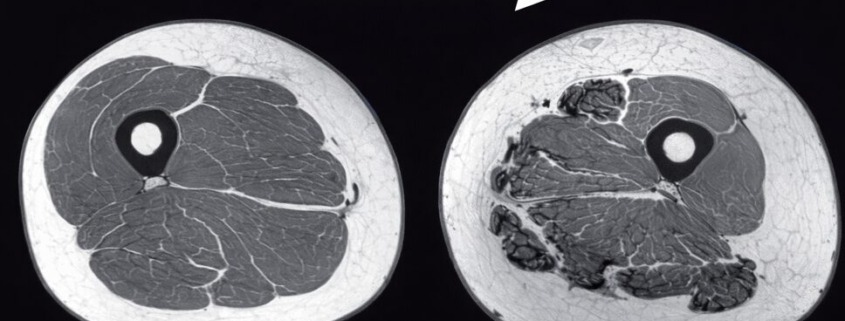

Mit zunehmendem Alter verlieren wir Muskelmasse – das gilt als selbstverständlich. Doch das ist ein Irrtum. Muskelabbau (Sarkopenie) ist keine unvermeidliche Alterserscheinung, sondern meist das Ergebnis stiller Entgleisungen: zu wenig Eiweiß, zu wenig Reiz, zu wenig Regeneration. Die hier unten (und auch oben im Beitragsbild) gezeigte MRT Aufnahme zeigt, wie dramatisch das aussieht:

Vergleich MRT-Querschnitt Oberschenkel: Frau 40 Jahre mit hoher Muskelmasse vs. Frau 75 Jahre mit Sarkopenie und Fettinfiltration